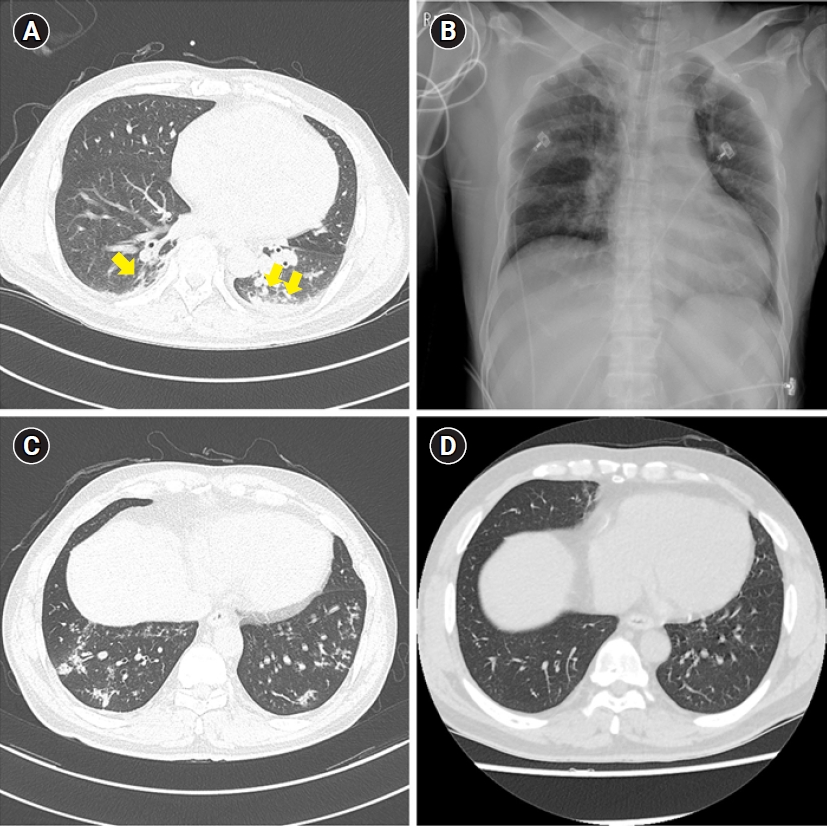

- Highresolution CT scans show wall thickness.

| HRCT | Wall thickness, airway lumen | Noninvasive |